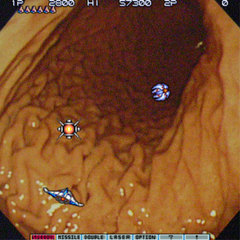

ちゅーわけで、ちょっと呆れられながらも、無事、自分の胃の写真をゲットしたのであった。ただ、そのまま載せるっつーのも、いくらなんでもちょっとアレなので、照れ隠しに「沙羅曼蛇」っぽくしてみるのである。Destroy them all!!